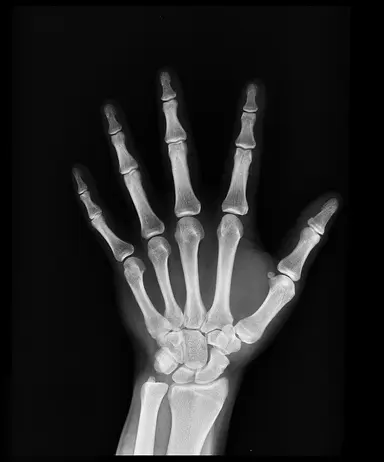

Q3.What is this type of image called?

Q5.This person has had an accident. Look at the X-ray, what can you see?